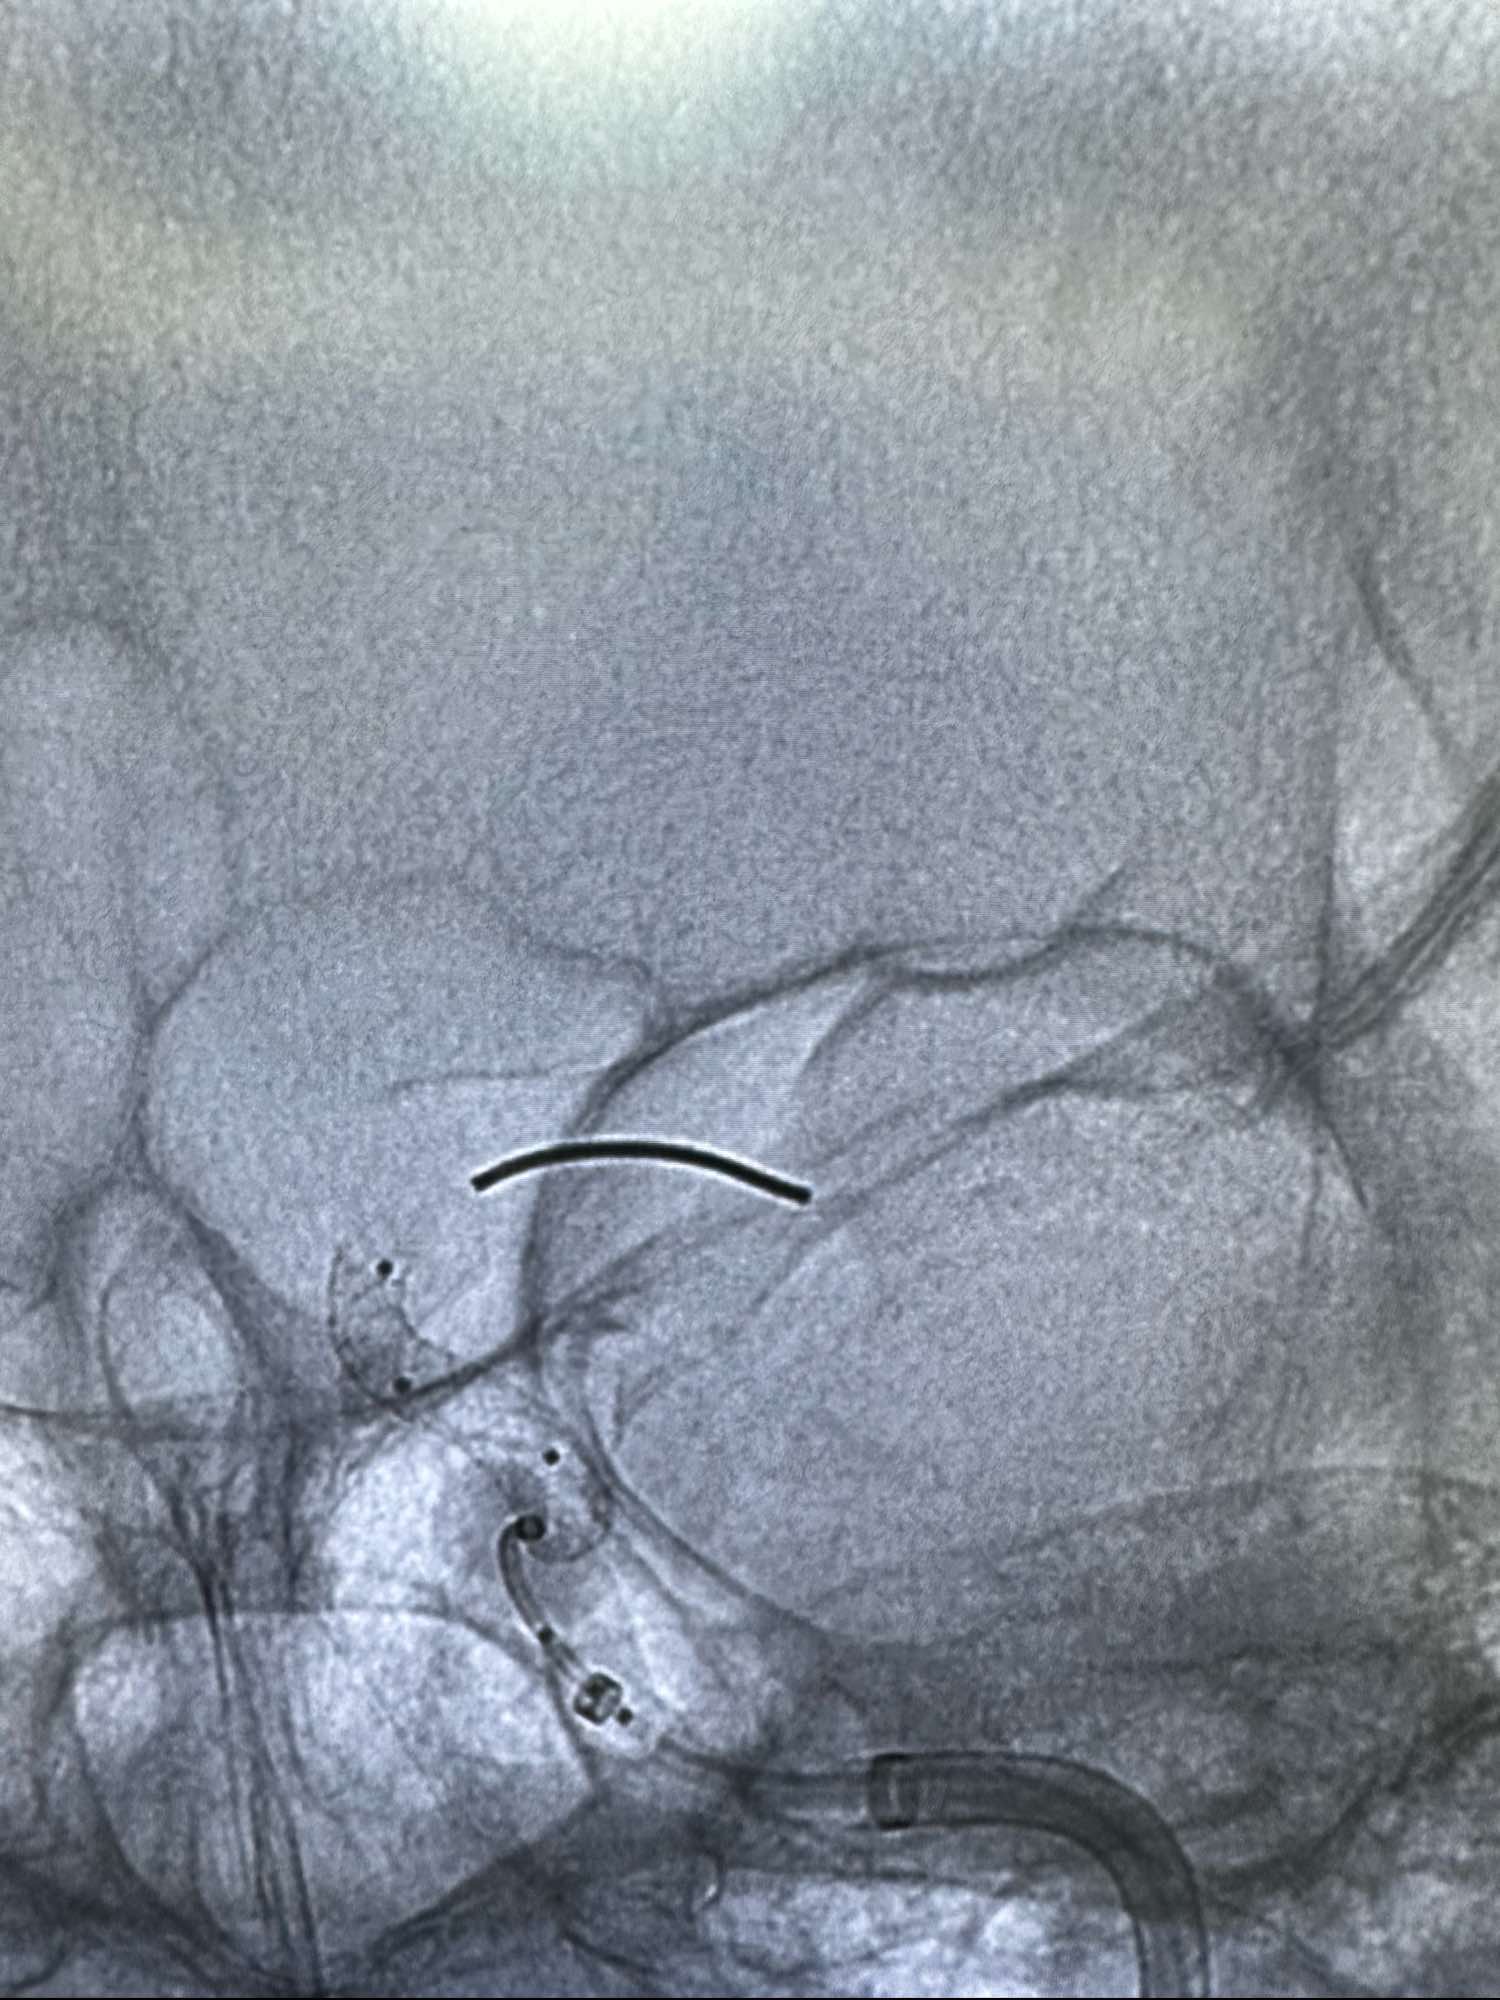

直接Neuromax长鞘加上5F的CAT 5F的115中间导管作为支撑

侧位

根据载瘤动脉的直径,选取4.4*20的Lattice的密网支架.进行原位释放.

支架在床突端打开不良,考虑血管扭曲,不停的进行支架摆动,最终打开